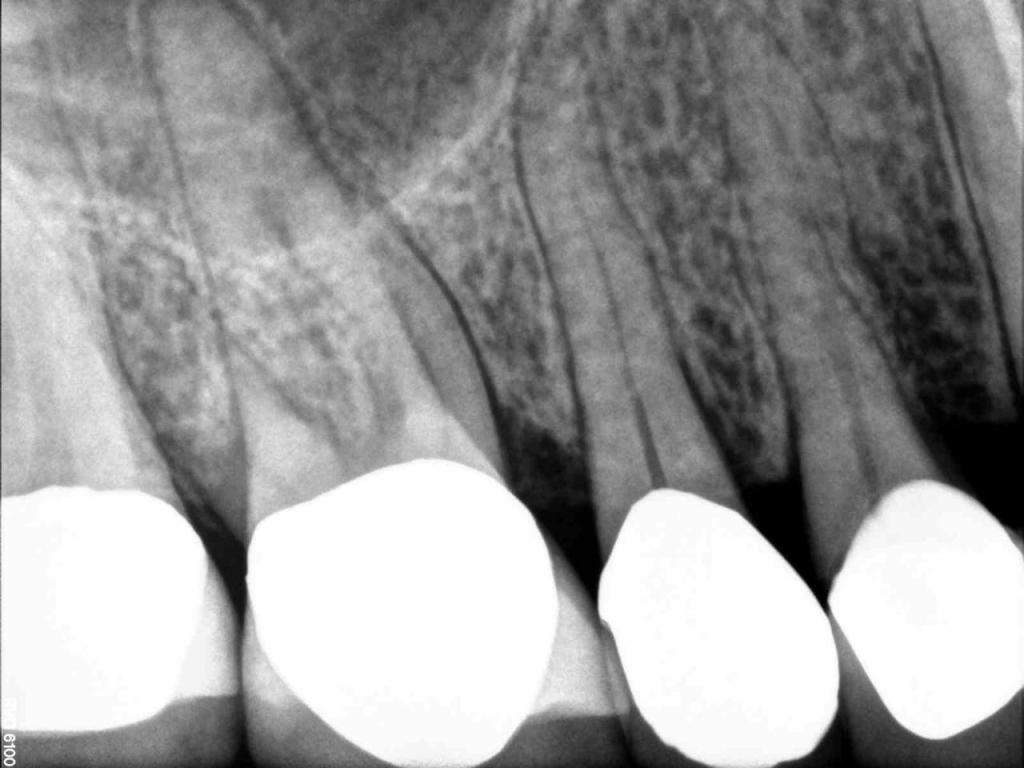

Although the primary use of visual documentation is for patient charts, dental images provide a meaningful way to communicate with patients about their care needs. Digital imagery is a vital tool for educating patients and an essential way to share information with office staff, colleagues and referring doctors. Digital technology has allowed Southcenter Endodontics to enhance our practice and improve the delivery of care to our patients. Below you will see images of “Before” and “After” scenarios. By clicking on a thumbnail image below, you will be able to see and a larger view of the x-ray taken at Southcenter Endodontics and notations made regarding each film.